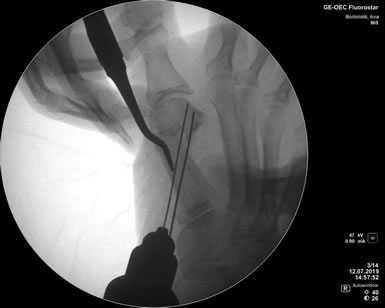

La cirugía Percutánea del pie, también conocida como cirugía MIS (Minimal Incision Surgery), permite realizar procedimientos quirúrgicos a través de pequeñas incisiones en la piel sin gran exposición ni trauma de tejidos.

De esta forma se disminuye el riesgo de complicaciones, como las lesiones de partes blandas, las infecciones y se obtienen menores tiempos operatorios, disminuyendo el dolor y acelerando la vuelta a la vida habitual.

Cirugia Percutanea Dr Masaragian